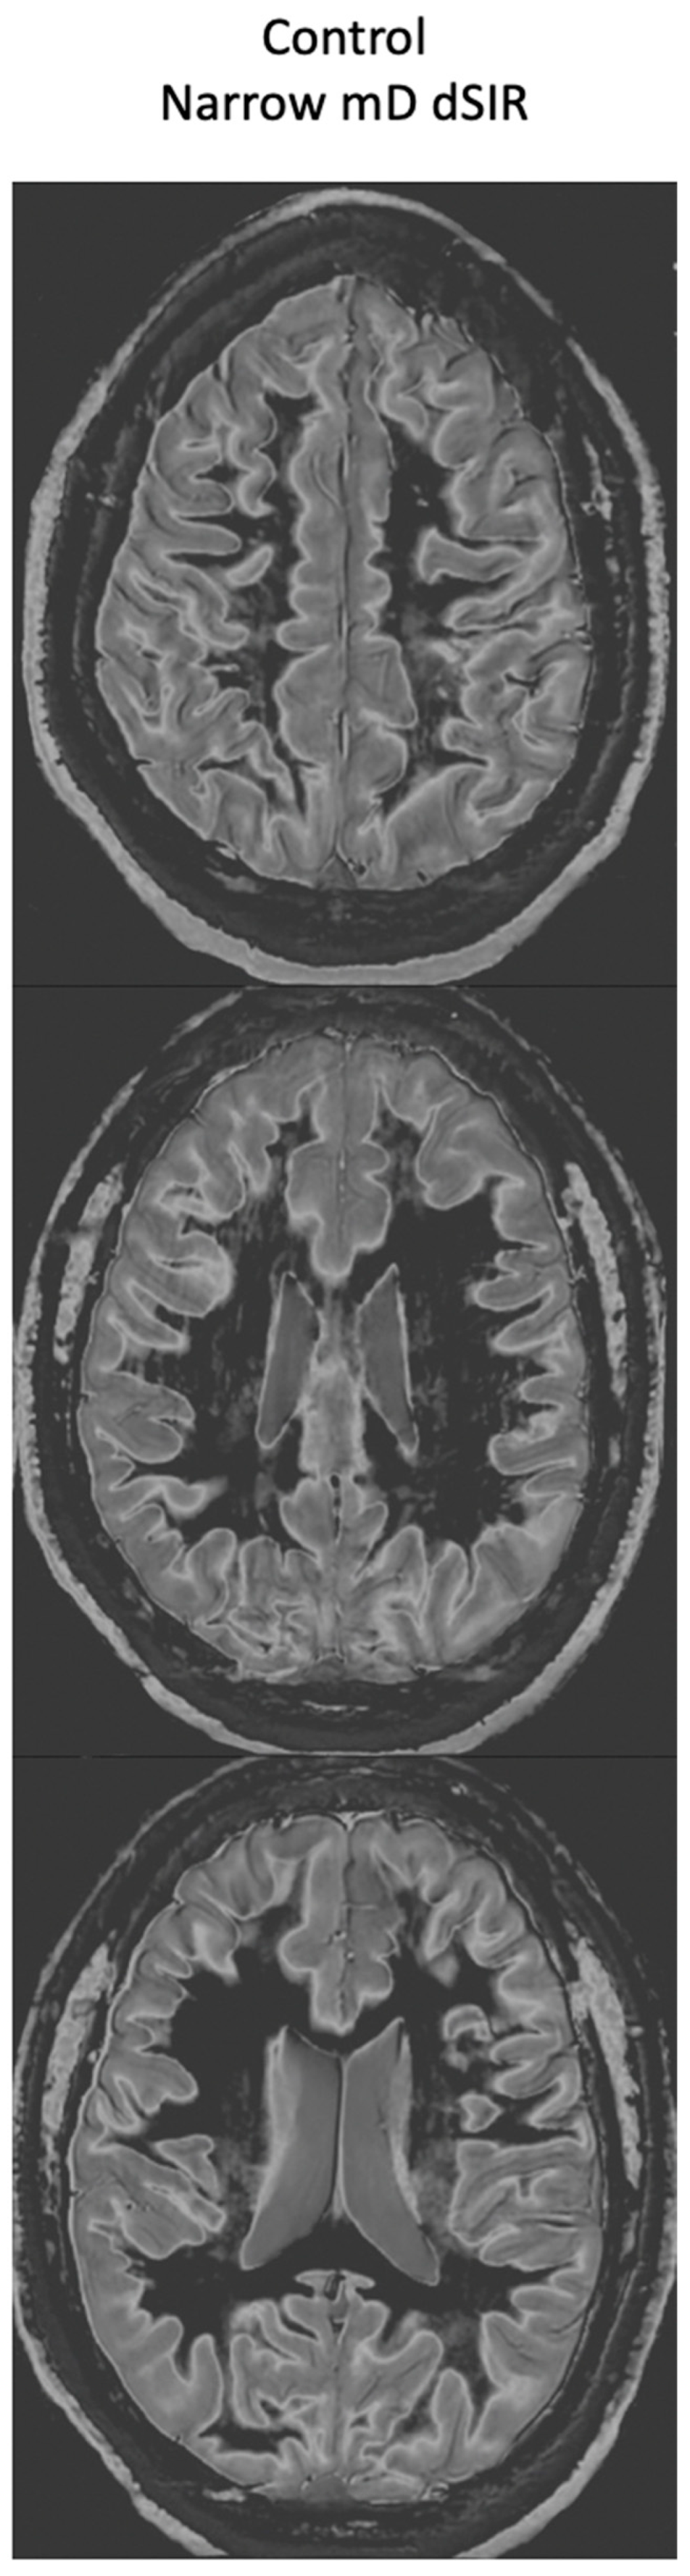

Figure 18 compares T2-FLAIR images (left column) with matched narrow mD dSIR images (right column) in Case 1 at the time of his first examination. No abnormality is seen in the white matter on the T2-FLAIR images (left column) but extensive high signal abnormalities are seen in white matter on the narrow mD dSIR images. Small areas of more normal white matter with a low signal appearance are shown by the white arrows (right column). These are features of a whiteout sign grade 4.

Figure 18.

Case 1 patient with methamphetamine use disorder. Comparison of T2-FLAIR and narrow mD dSIR images. No abnormality is seen on the T2-FLAIR images (left column) but there are extensive areas of higher signal in approximately 90% of the white matter (right column). Only small areas of normal low signal are seen in the white matter (white arrows) (right column). The appearances on the dSIR images are consistent with a whiteout sign grade 4.